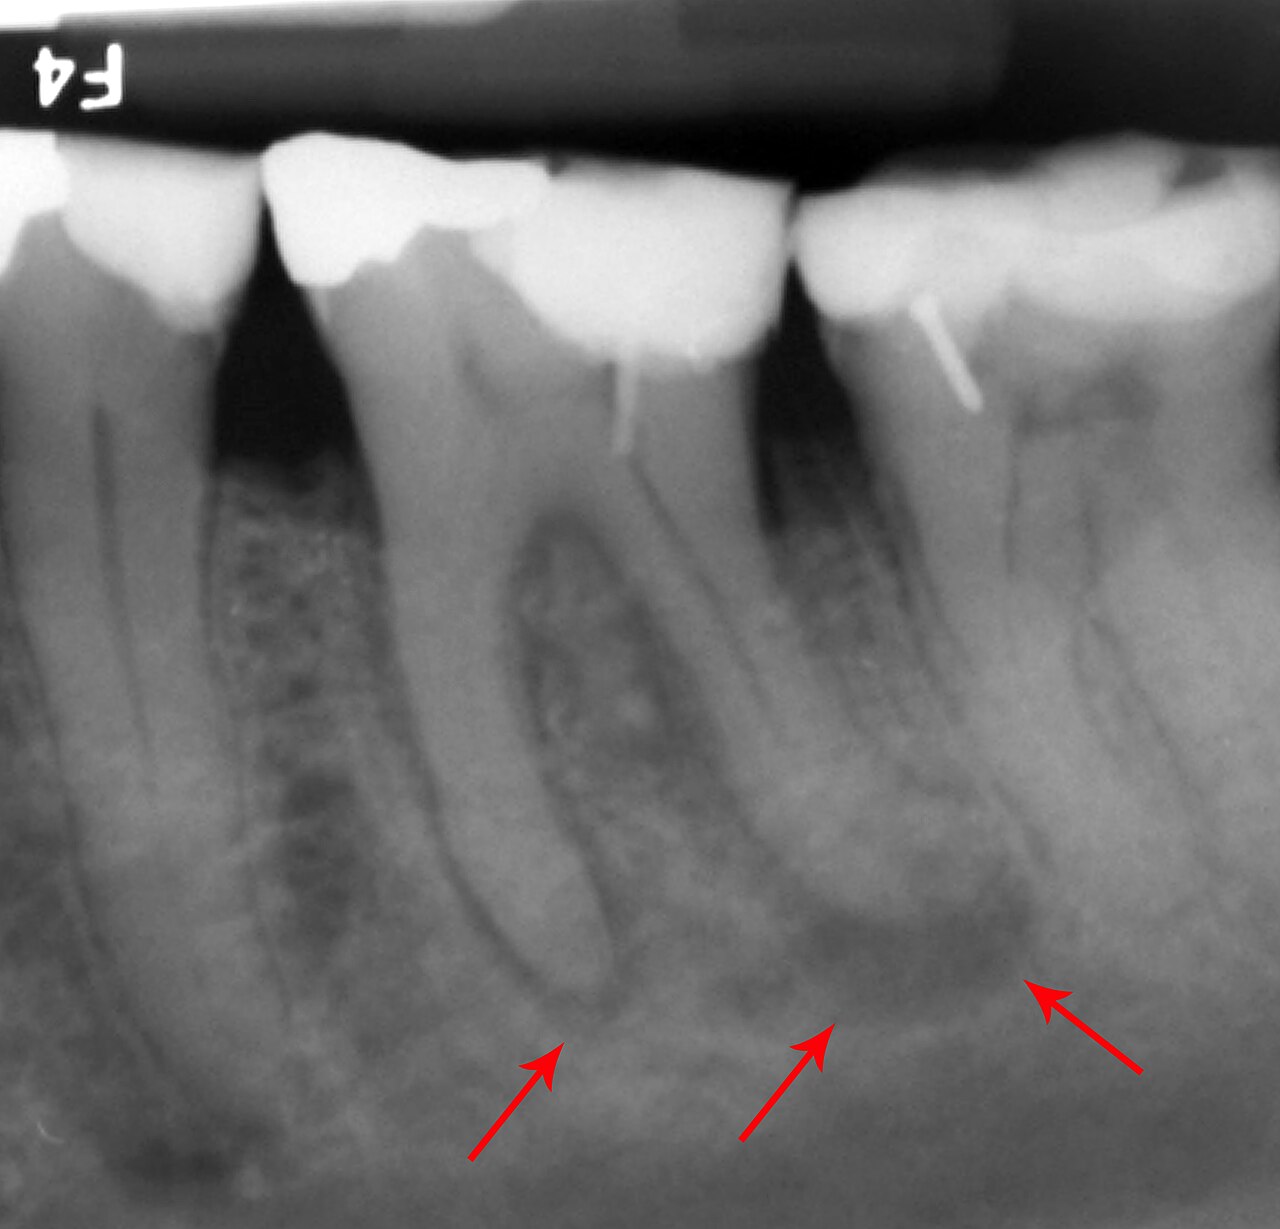

Dental phantom showing common pathology: carious lesions, periapical abscess, root resorption, and a metallic restoration

Periapical radiograph phantom showing 2-3 teeth with roots, periodontal ligament, alveolar bone, and surrounding...